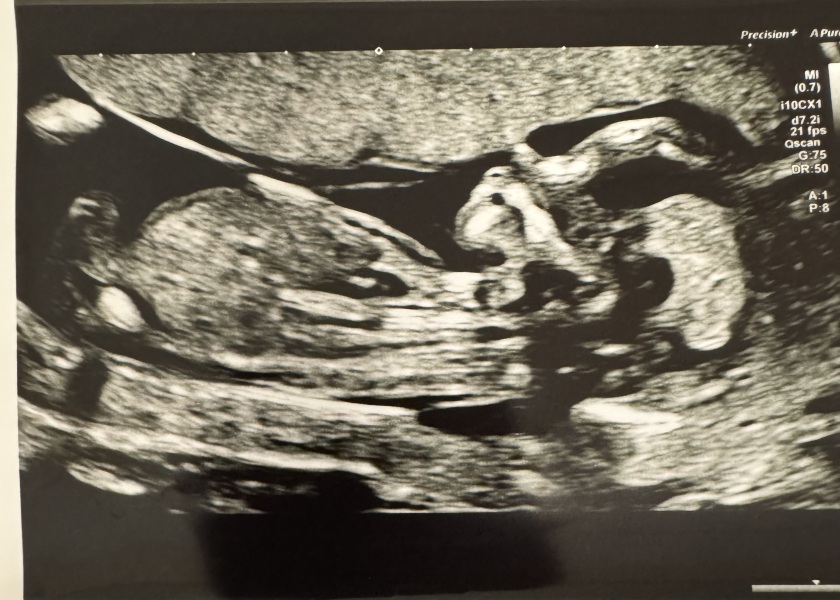

@Hotmalibu94 @Ncl31 @EK37 thank you all, still waiting to do my bloods but we’ve seen little bub now and all seems good so far 🥰 due date didn’t change either so still bang on the same and 13w+4 days

Our little wiggly little bub. They were having a hard time taking a picture as baby kept moving around 😂

@Hotmalibu94 very excited! All seems good for now just have to wait for the blood results in a few weeks but the NT measurement was good.